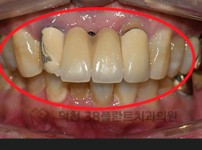

치료전후